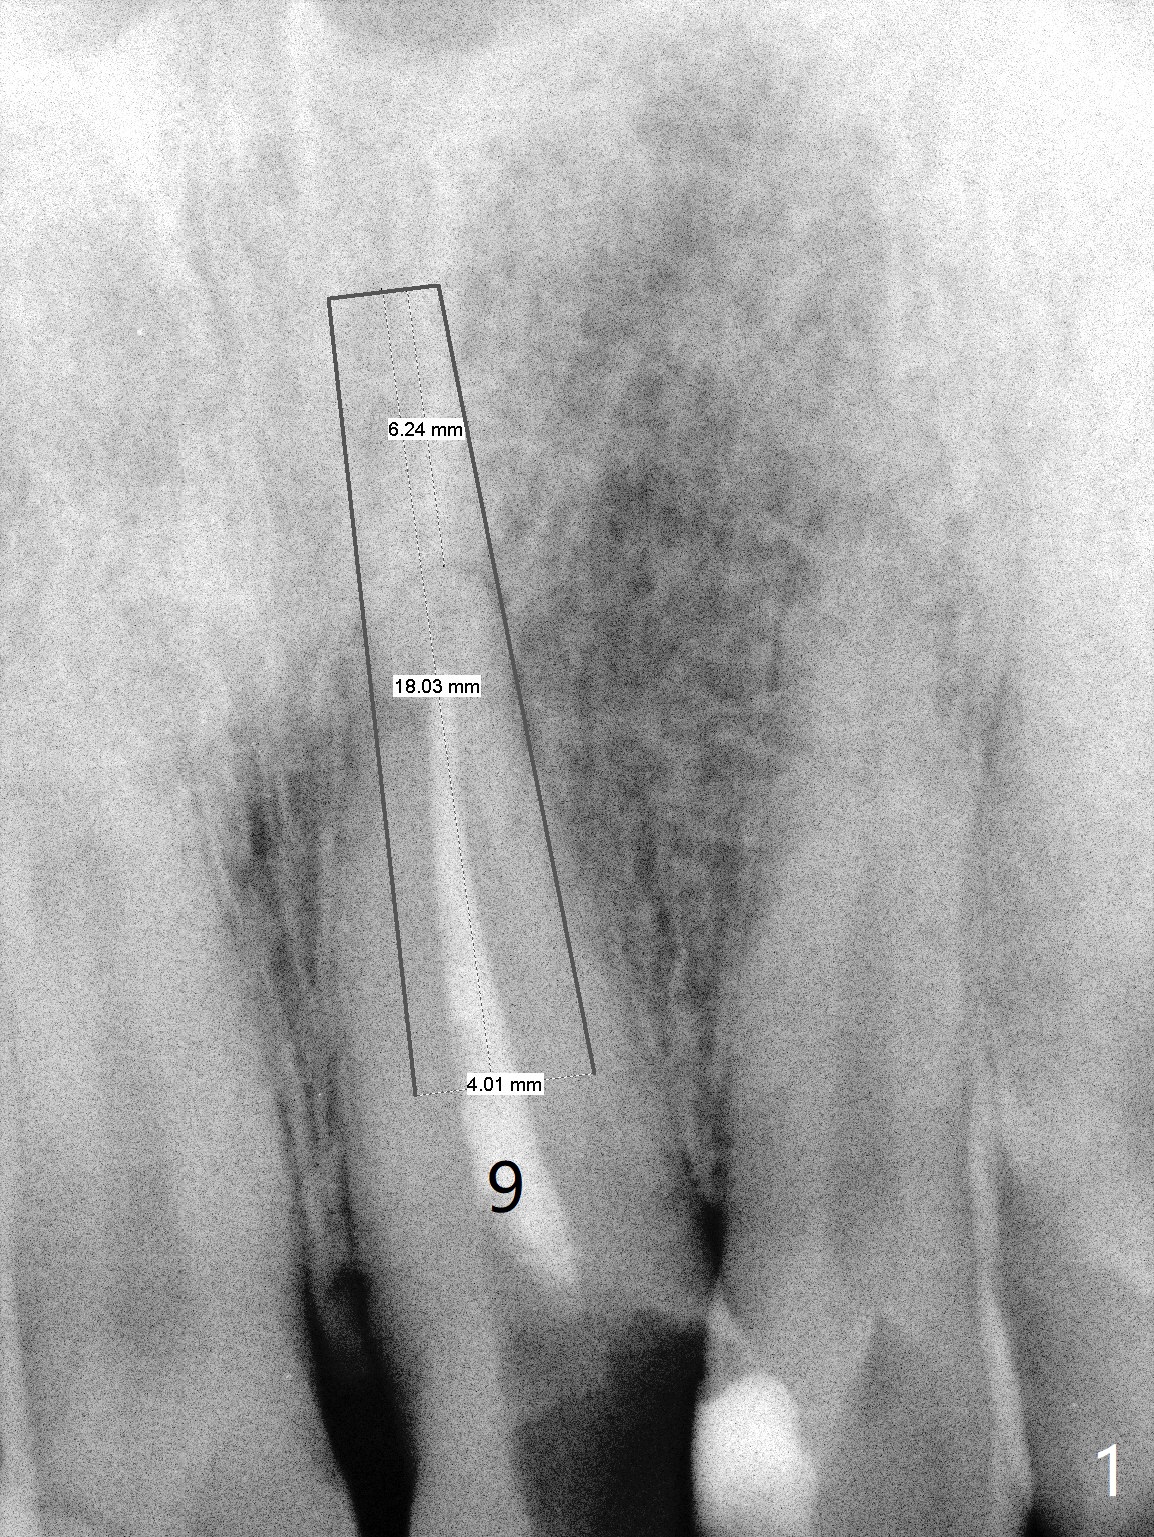

Longest Bone-Level Implant

A 56-year-old man, bruxer, has multiple restoration. After tooth fracture at #9 (Fig.1), a post-supported crown is fabricated (Fig.2). The post/crown dislodges once, while the post fractures recently. To counter heavy mastication, a long implant will be placed. Take preop photos.